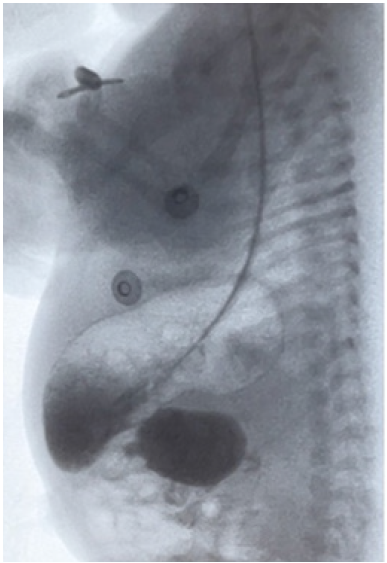

Presenta vómitos biliosos en las primeras 12 horas de vida, por lo que se coloca semisentado, sonda nasogástrica (SNG) y se suspende vía oral. En Rx de abdomen se evidencian estómago y duodeno francamente dilatados (imagen en “doble burbuja”) (Figura 2) con gas distal en pelvis. Franca mejoría del cuadro clínico y se inicia nutrición parenteral.

Figura 2 EGD paciente, imagen en “doble burbuja” y el pasaje filiforme.

Estudio contrastado de esófago-gastro-duodeno (EGD) a los cinco días de vida evidencia estómago y duodeno 1 dilatados y un pasaje filiforme intermitente a duodeno 2.